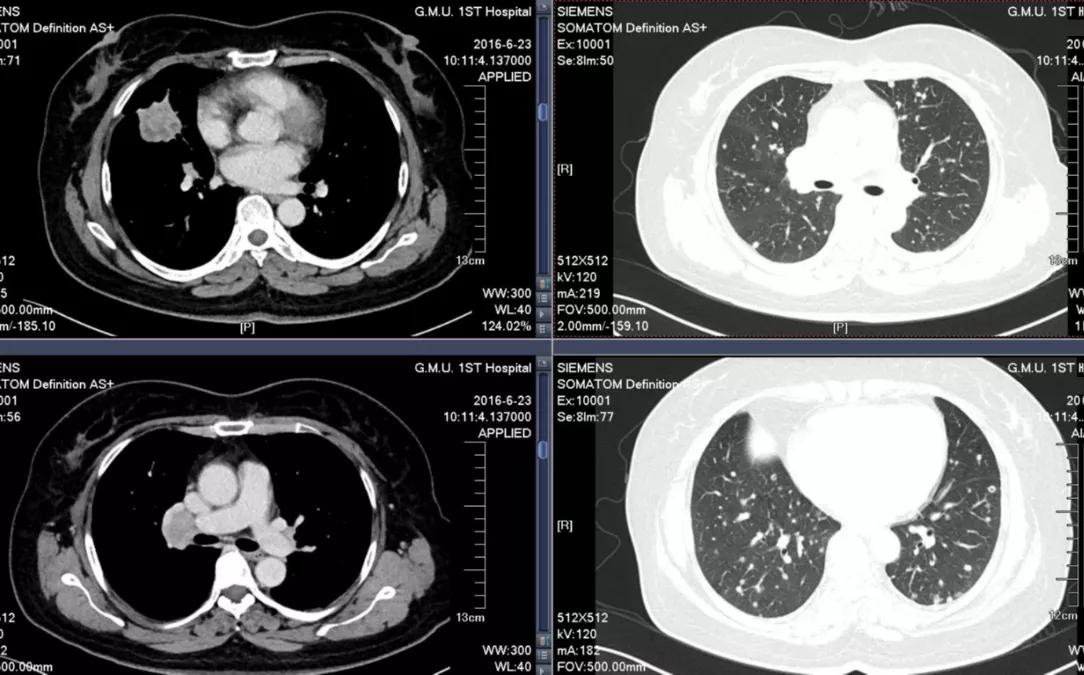

√ 2016-6-23

胸腹部CT诊断:

1.考虑右中肺肺癌并两肺多发转移瘤,右肺门、纵膈淋巴结转移。

2.左肾下极小囊肿;余上腹部CT平扫及增强未见明确病变。

胸部CT显示:右中肺肺癌并两肺多发转移瘤,右肺门、纵膈淋巴结转移。